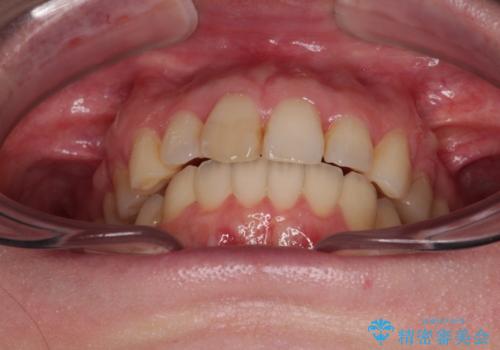

カリエール・ディスタライザーを用いたことで上顎前歯の突出感はスムーズに解消され、歯列不正は1年半ほどでほぼ改善することができました。

しかし、その後インビザライン特有の奥歯がうまく噛めないという問題が長引き、改善に1年近い期間を要することとなりました。